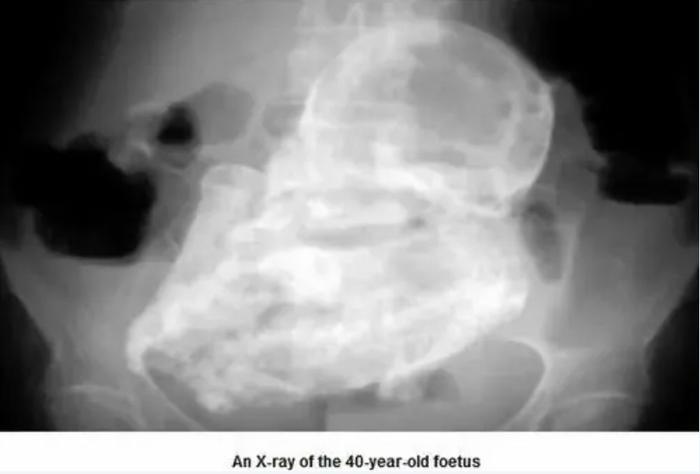

因为胎儿去世后一直留在腹部,免疫系统认为这只死胎对身体构成了威胁,对它发起猛烈攻击,于是,含钙的沉积物沉积在胎儿身上,逐渐将它包裹在钙化壳中,变成一块形似木乃伊的“石头”,也就是医学文献中记载的罕见出现的“石胎”。

根据目前的医疗病例记录,全世界出现过的“石胎”病例还不到300例。而且医学文献称,石胎对人体的影响因人而异,它可能不会引发任何症状,可以在体内保存长达60年不被察觉,也可能影响胃肠道和泌尿生殖系统。

曾经有一位被诊断怀有石胎的智利老人,92岁的埃斯特拉·梅伦德斯,就在不知情的情况下带着死胎生活了整整50年…

一直以来,医生的诊断都是她的腹中长了一个小“肿瘤”,直到92岁时因摔跤再次入院,这颗“肿瘤”才被发现是已经钙化的胎儿,胎儿重约2公斤,是一次流产手术的遗留物,但多年来她除了再没有生育,身体没有受到其他影响。